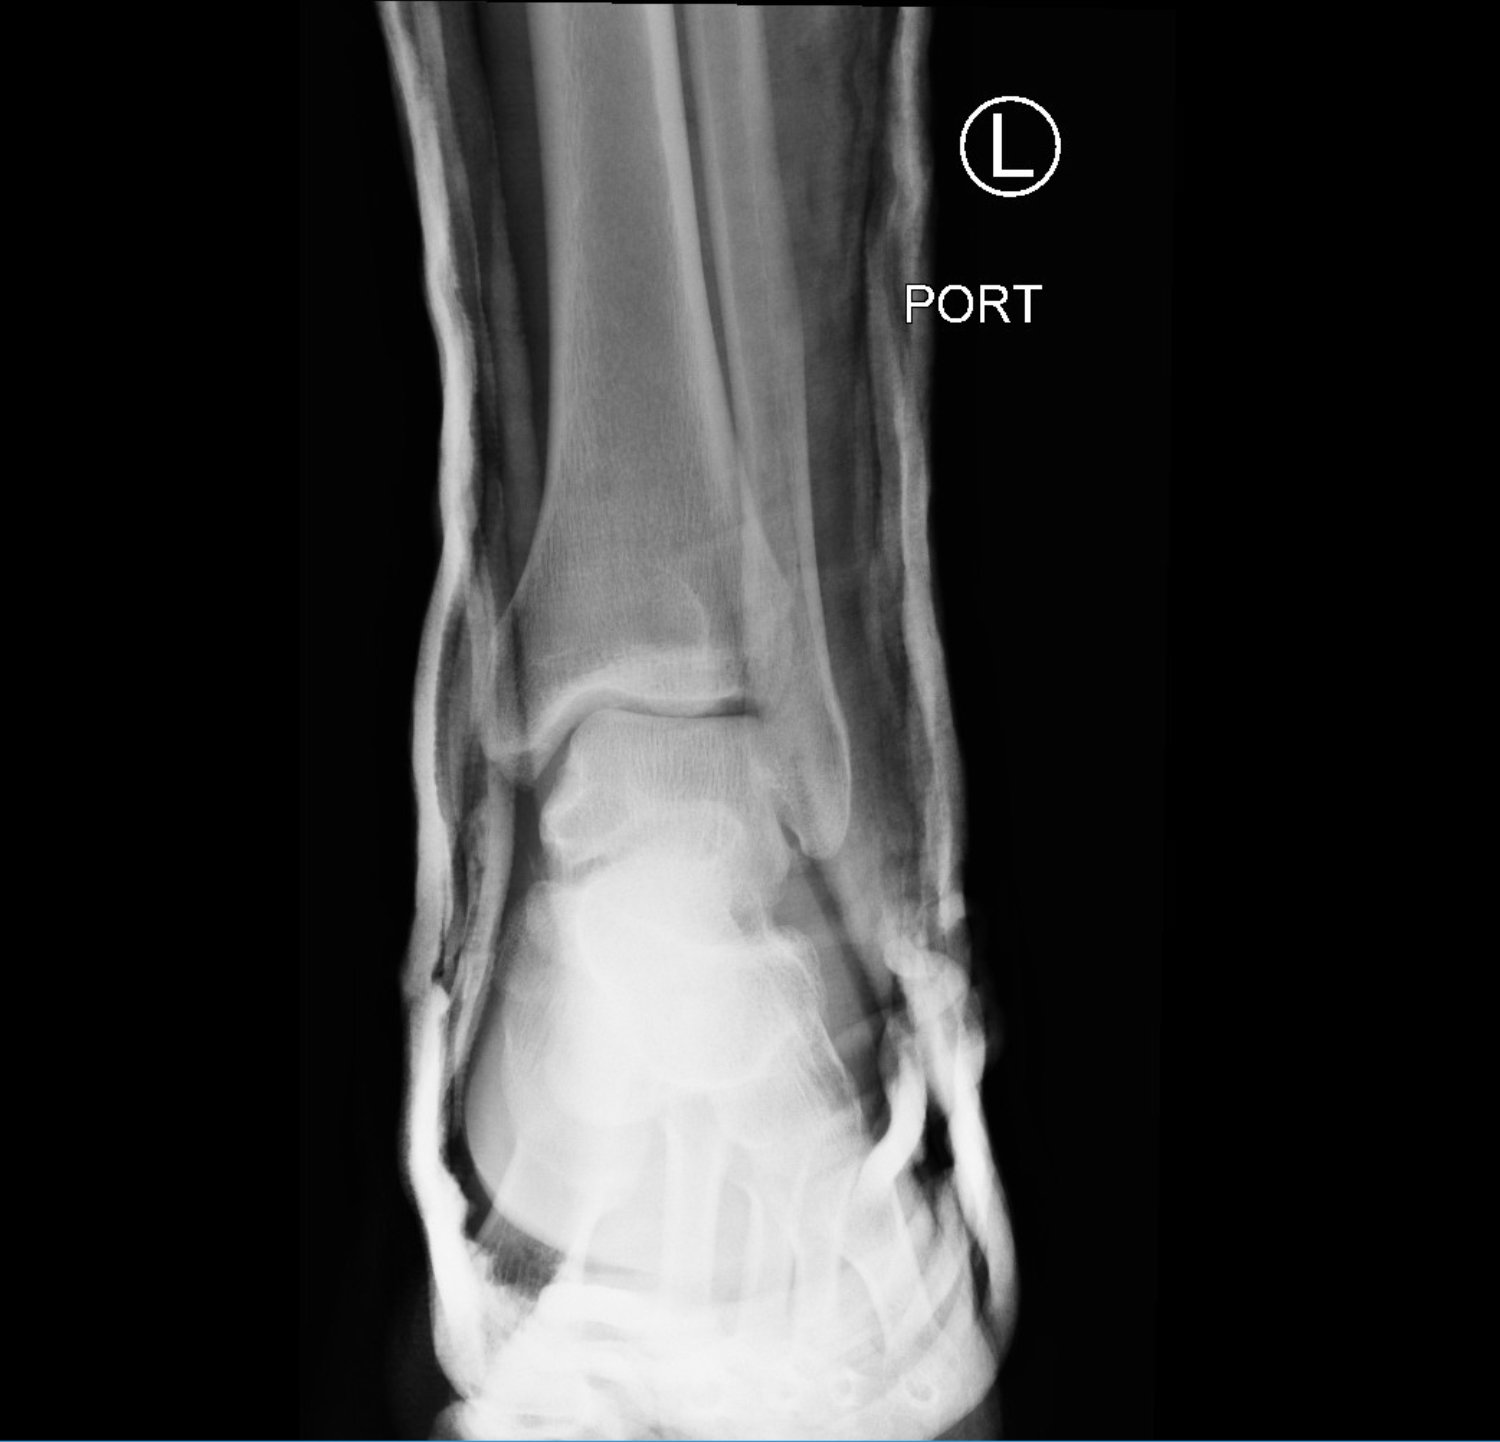

Subtalar dislocation is an unusual form of joint injury from high-energy trauma or athletic injuries. This case report describes a 22-year-old male who presented to the emergency department with left ankle pain after falling from his bicycle. Examination revealed significant deformity of the left foot and ankle. The foot pointed medially, and the bottom portions of the tibia and fibula were visible with the overlying skin intact. Radiographs confirmed left medial subtalar dislocation. There was no neurovascular compromise of the foot. The dislocation was successfully reduced under procedural sedation and the patient’s left leg was placed in a splint. He underwent post-reduction imaging and was instructed to remain non-weight-bearing and to follow up with orthopedics to discuss further management. The purpose of this report is to describe a case of a closed, medial subtalar dislocation and the approach to management.